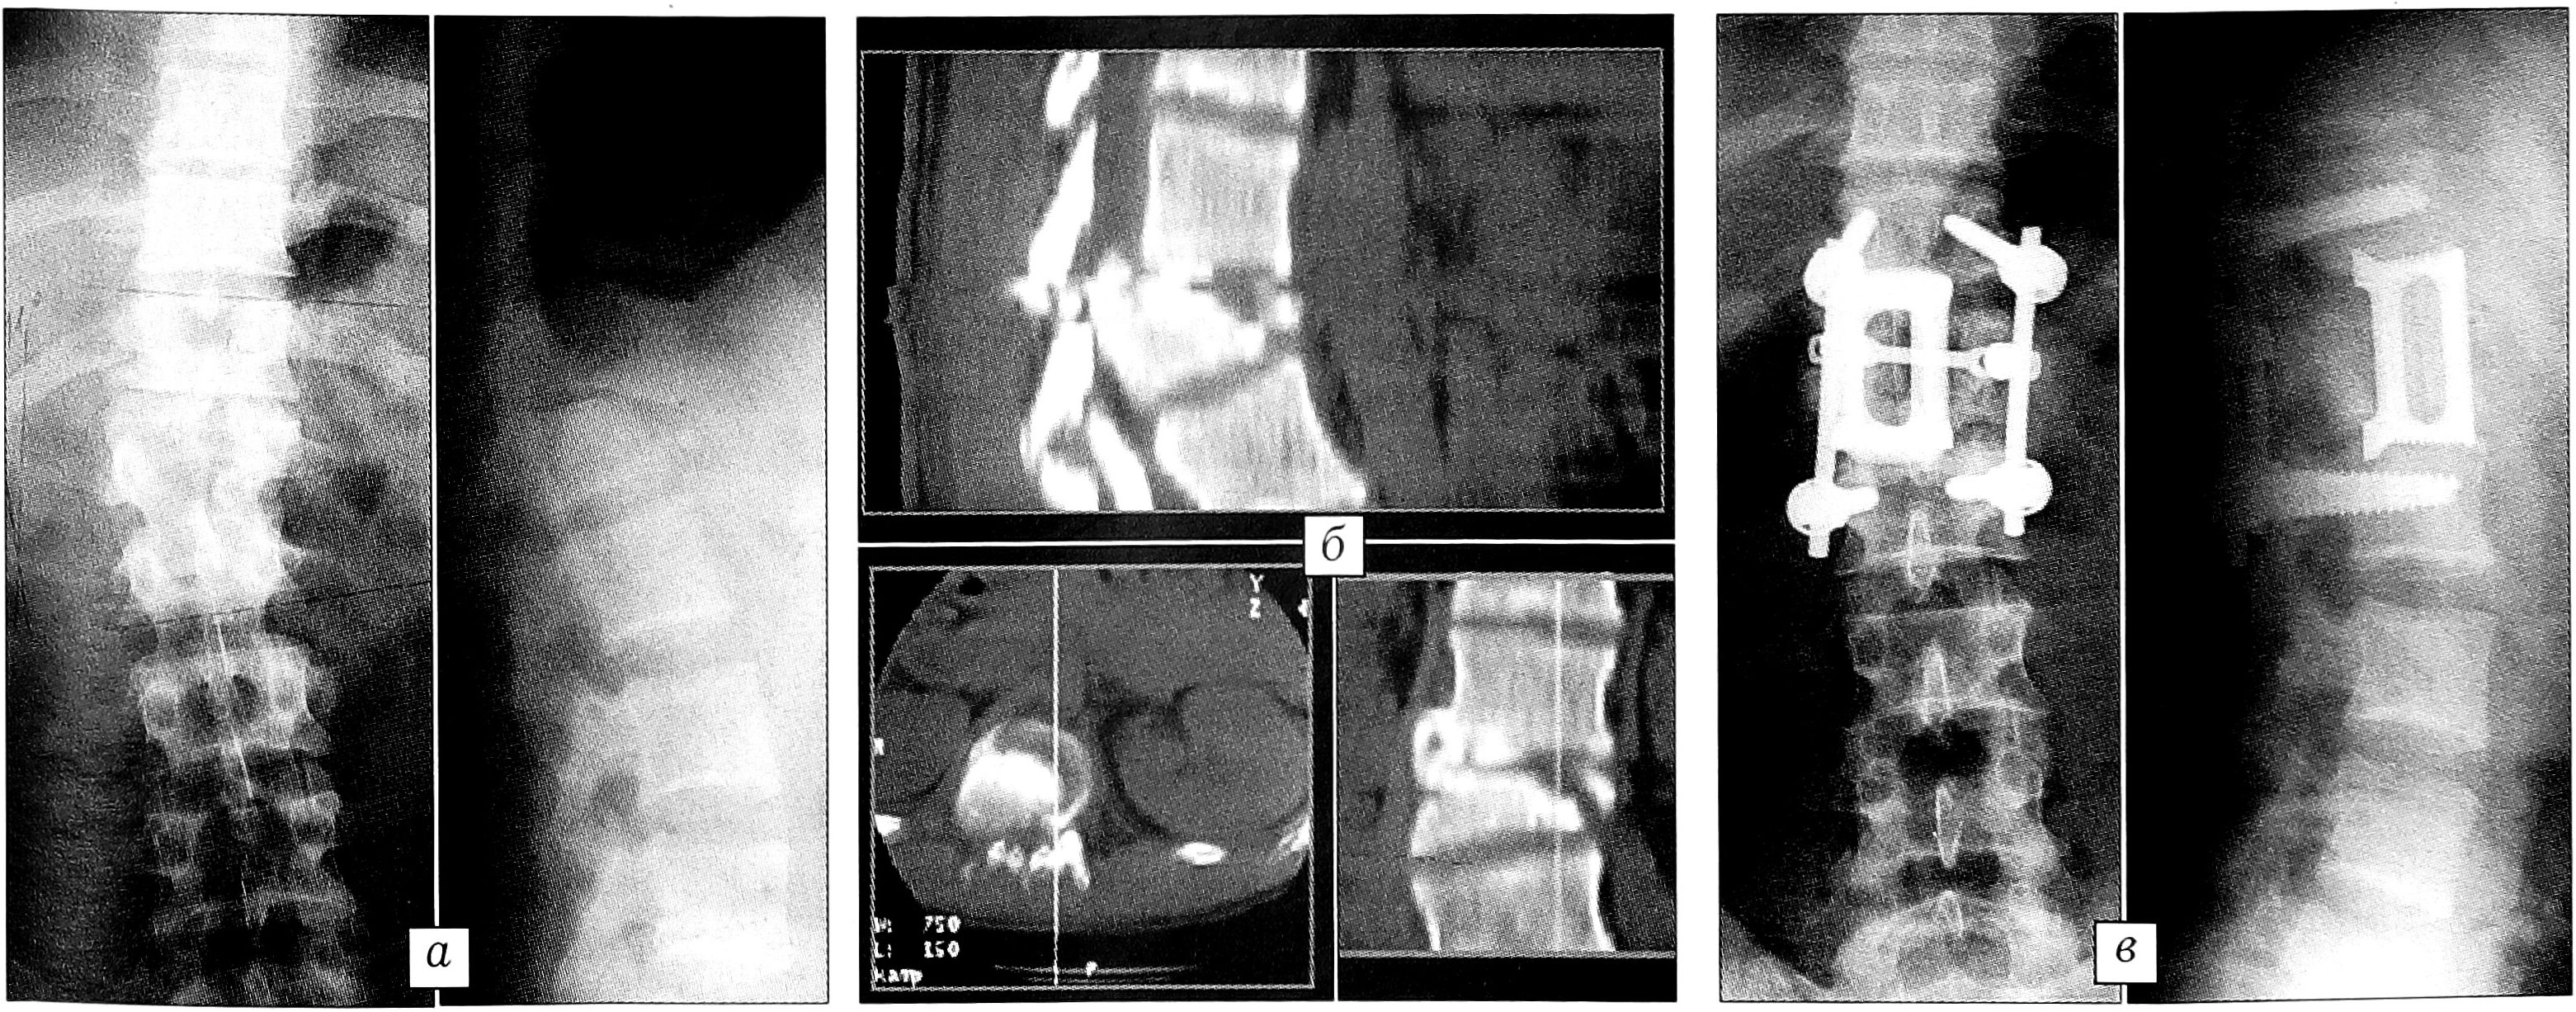

Стабильные проникающие компрессионные, взрывные неполные и полные переломы тел позвонков, тип А. Такие стабильные переломы, особенно с выраженной осевой деформацией и дислокацией дорсального фрагмента в позвоночный канал без одновременного разрушения средней и дорсальной колонн, требуют оперативного лечения. Консервативные методы лечения, дорсальная фиксация различными конструкциями, применяемые многими травматологами, как правило, не устраняют посттравматическую деформацию и не обеспечивают благоприятного исхода. Методом выбора при проникающих компрессионных, взрывных стабильных переломах тел позвонков (типа А) является корригирующий вентральный спондилодез, при необходимости с передней декомпрессией и, в зависимости от повреждения одного или двух сегментов, с моносегментарной (рис. 1) или бисегментарной (рис. 2) эндофиксацией. Характер, обем операции, особенности коррекции деформации сломанного позвонка, передней декомпрессии, размеры моно-, бисегментарного коронарного эндофиксатора определяются при предоперационном планировании по данным рентгенографии, компьютерной томографии. Во время операции полностью исправляется осевая деформация и восстанавливается высота травмированного позвоночного сегмента (см. рис. 1, в и рис. 2, в).

Рис. 2. Больная К. 47 лет. а — рентгенограммы до операции: взрывной перелом тела Т12 позвонка, кифосколиотическая деформация; б — компьютерная томограмма до операции: дислокация дорсального фрагмента в позвоночный канал; в — рентгенограммы через 1 год после коррекции кифосколиоза, передней декомпрессии, аутопластики, бисегментарной эндофиксации.

Оптимальный срок проведения операции — первые 7-10 дней после травмы. Используемые нами оригинальные коронарные эндофиксаторы (пат. 2133596 РФ, регистрационное удостоверение № 29/12020201/2886-01 в Государственном реестре медицинских изделий) создают после коррекции стабильную фиксацию поврежденного сегмента в течение всего периода формирования межтелового костного блока, предотвращая рецидив деформации позвоночника. При этом продолжительность постельного режима после операции сокращается до 2-3 нед, пациенты избавляются от длительной иммобилизации корсетом, обеспечивается возможность более функционального полноценного восстановительного лечения.